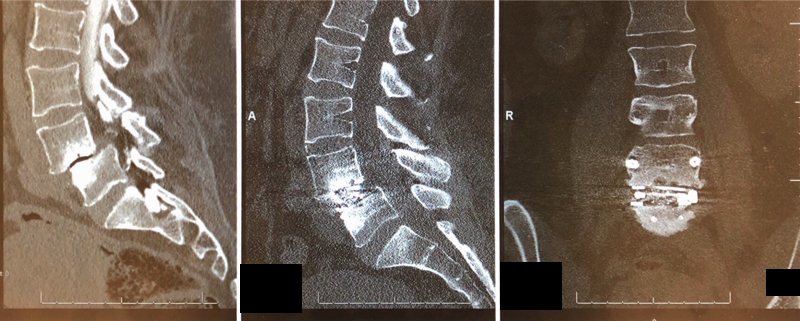

Left and middle: spondylolisthesis. Right: anterior view of the spine following fusion surgery.